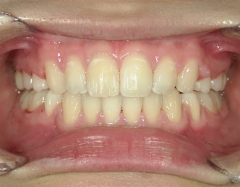

矯正歯科 治療前

矯正歯科(全顎ワイヤー矯正)治療後

矯正歯科 治療後